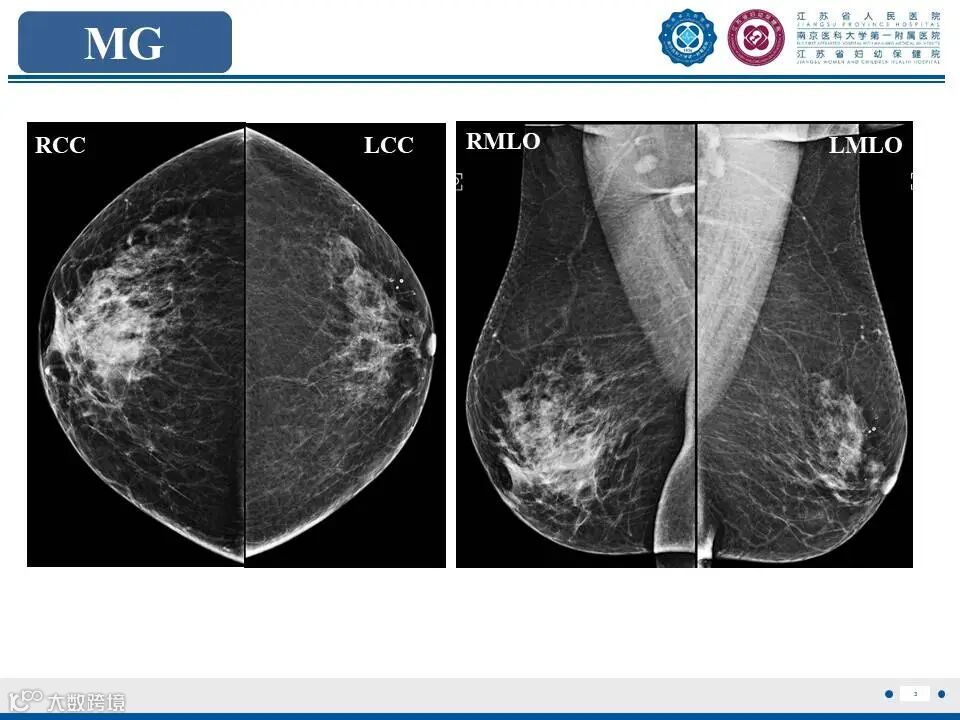

非哺乳期乳腺炎